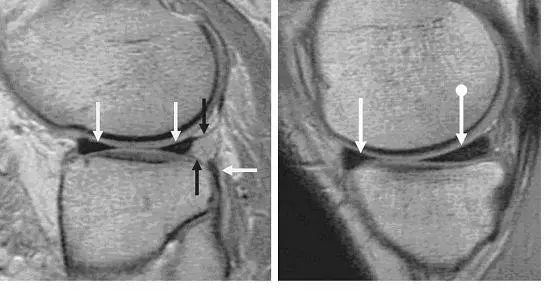

强直性脊柱炎有什么影像学表现?

X 线检查对 AS 的诊断有极为重要的意义,早期几乎都有骶髂关节炎表现,病变一般在骶髂关节的中下部开始,为两侧性。

开始多侵犯髂骨侧,进而侵犯骶骨侧。可见斑点状或块状,髂骨侧明显,继而侵犯整个关节,边缘呈锯齿状,软骨下有骨硬化,骨质增生,关节间隙变窄,最后关节间隙消失,发生骨性强直。

脊柱病变的 X 线表现早期为普遍性骨质疏松,椎体呈「方形椎」,最典型的表现是「竹节样改变」,T10-L2 较常见,腰椎呈「鱼尾椎」改变。